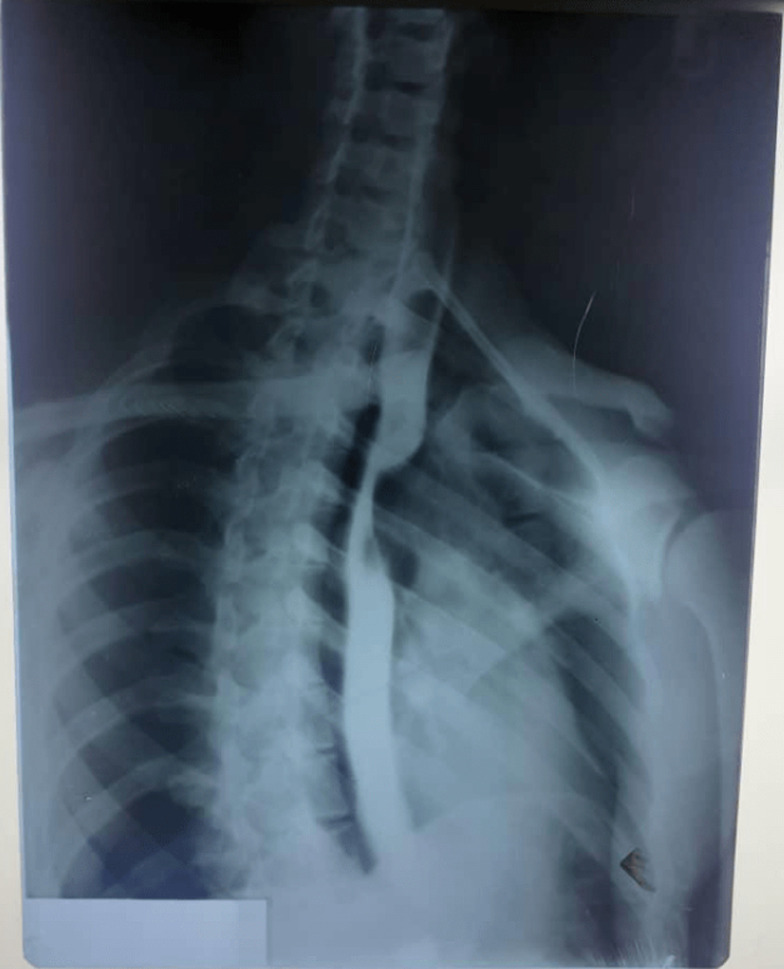

Anomalies of the arterial branches of the arch of the aorta are rare, with the aberrant right subclavian artery being the most common of this anomaly. Majority of the anomalies are asymptomatic and often discovered as incidental findings. In the great majority of the symptomatic cases, the presentation may be either with breathlessness or dysphagia or both. This is in addition to the nature of the intrinsic arterial disease of the aberrant vessel, especially in adult patients; and unless borne in mind, the diagnosis is often missed leading to delays and wrong treatment. In this report we present a case of dysphagia in an adult male Nigerian initially diagnosed as œsophageal stricture from herbal potion ingestion but review of his imaging investigations gave a final diagnosis of dysphagia lusoria from an aberrant right subclavian artery. The difficulty in making a diagnosis and the need for a multidisciplinary review of the imaging investigations are highlighted. The patient was successfully treated by a combined trans-thoracic and cervical approach with division and re-implantation of the aberrant vessel unto the right common carotid artery. He has remained symptom-free for 2 years after surgery. Although the great majority of these anomalies are often asymptomatic, it is important they are borne in mind both in imaging investigations as well as in procedures involving structures in the upper visceral mediastinum. Various surgical approaches have been documented in the management of symptomatic ones; it is however recommended that options that ensure revascularization of the affected limb be selected.

Abstract Image